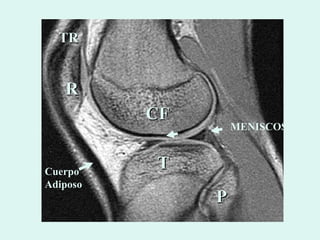

R CF T P TR MENISCOS Cuerpo Adiposo

R CF TP TR MENISCOS Cuerpo Adiposo